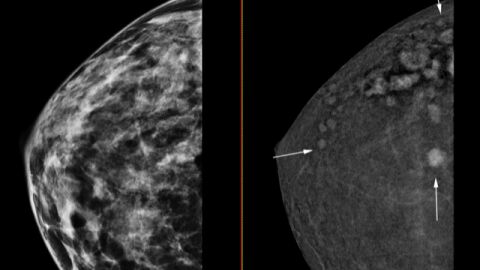

El Hospital Universitario del Vinalopó ha adquirido un mamógrafo 3D con contraste que permite la detección de tumores de un tamaño de apenas 4 milímetros, que con la tecnología convencional son invisibles.

Con ello, ese mamógrafo 3D con contraste es capaz de detectar hasta un 30% más de tumores cancerígenos.